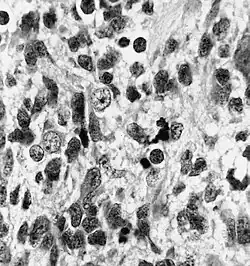

| Histopathology of medulloepithelioma showing characteristic neural tube like strands. | |

Histologically, medulloepithelioma resemble a primitive neural tube and with neuronal, glial and mesenchymal elements.[8][9] Flexner-Wintersteiner rosettes may also be observed.[10]

Immunohistochemically, neural tube-like structures are vimentin positive in the majority of medulloepitheliomas.[11] Poorly differentiated medulloepitheliomas are vimentin negative.